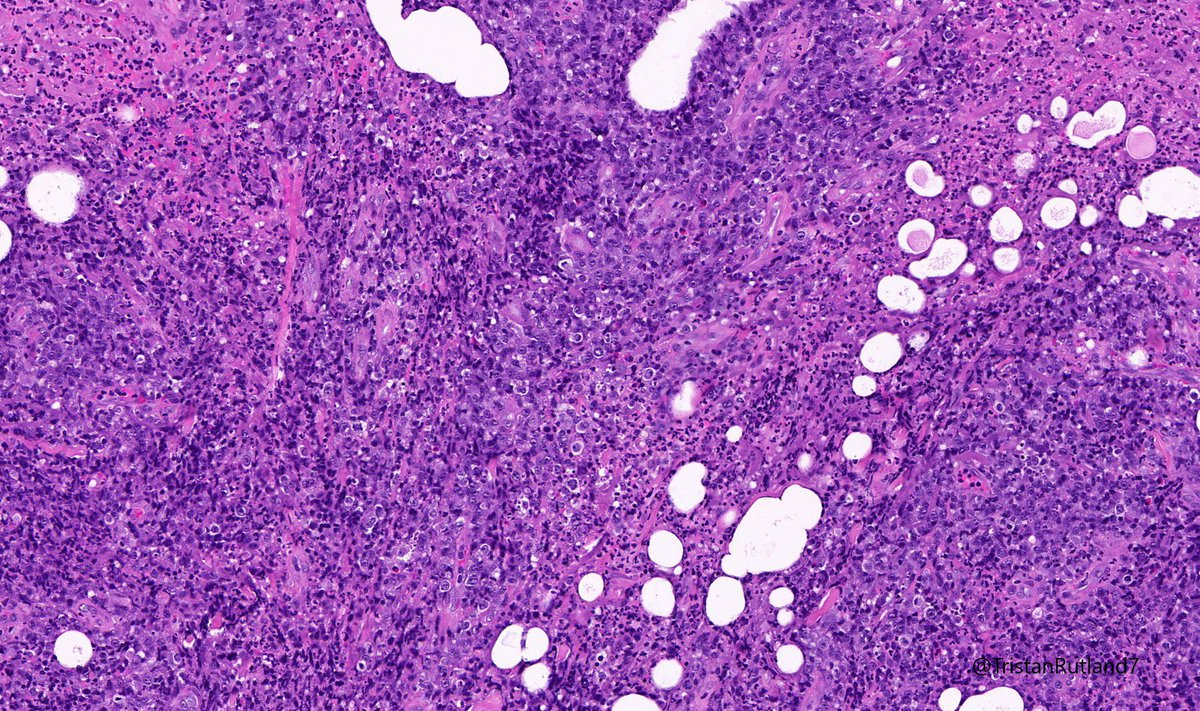

Female, adult, leg.

Large cell transformation of mycosis fungoides (MF).

3/ Large cell transformation is defined by greater than 25% large cells (4X size normal lymphocytes) or nodular aggregates in dermis.

4/ It usually arises from tumour stage (rare cases arising from patch stage have occurred).